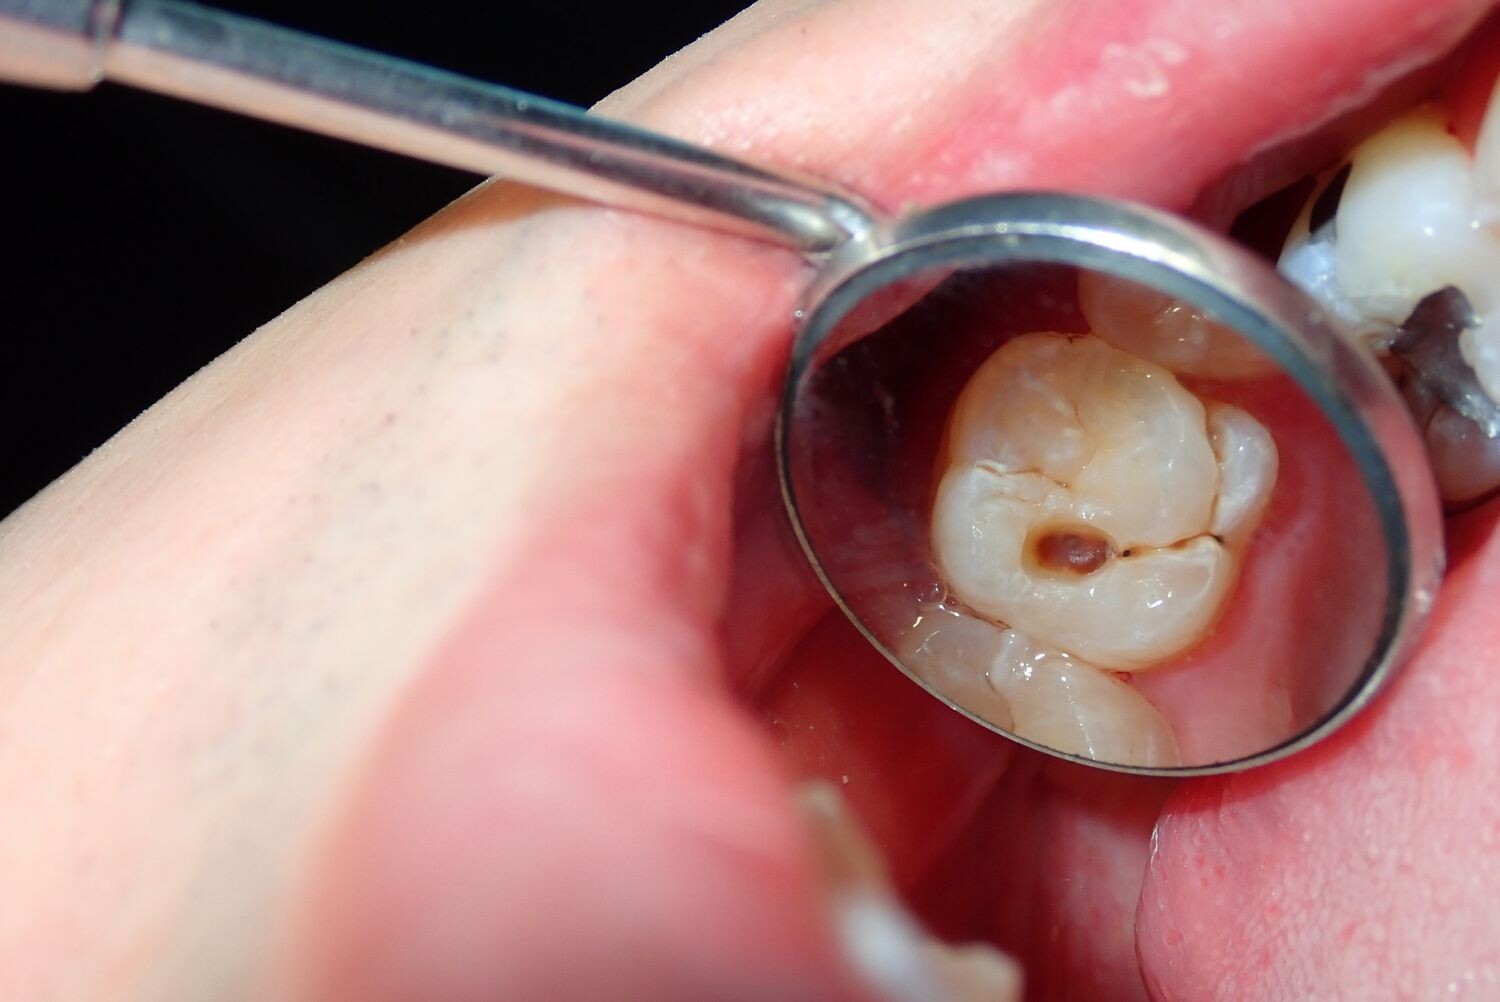

Cavities are pretty common. As the National Institutes of Health points out, the only condition more common than a cavity is the common cold. If you've never experienced tooth decay, you might wonder, "What does a cavity feel like?" The answer depends on the stage of the cavity and what foods you eat. Some foods, such as sweets, might trigger the pain of a cavity more than others.

How Cavities Form

Your mouth is naturally full of germs. Some of those germs are perfectly healthy, but others can be harmful. When you eat something sugary, such as candy or even potato chips, or drink a sugary beverage, the germs feed on the sugars in the substance. This produces acid, which is strong enough to wear away tooth enamel if not cleaned off quickly enough. In the end, a dental cavity begins to form.

Signs of a Cavity

What does a cavity feel like? In the earliest stages, the answer might be nothing. There are no nerves in your tooth enamel, so when the decay is in that layer, you likely won't feel a thing. Once the decay has progressed enough to reach the softer tissues inside the tooth, where the dentin and nerves are, you might notice signs of a cavity. Your teeth might feel sensitive and you could feel some pain, especially after eating sweets, hot foods or cold foods. The pain can be fairly mild or sharp and intense. Some people with cavities also feel pain when biting down.

Depending on the size of the cavity, you may be able to see evidence of it in your mouth. Cavities sometimes create visible holes in the teeth. They can also create stains that are black, brown or white on the surface of the tooth.